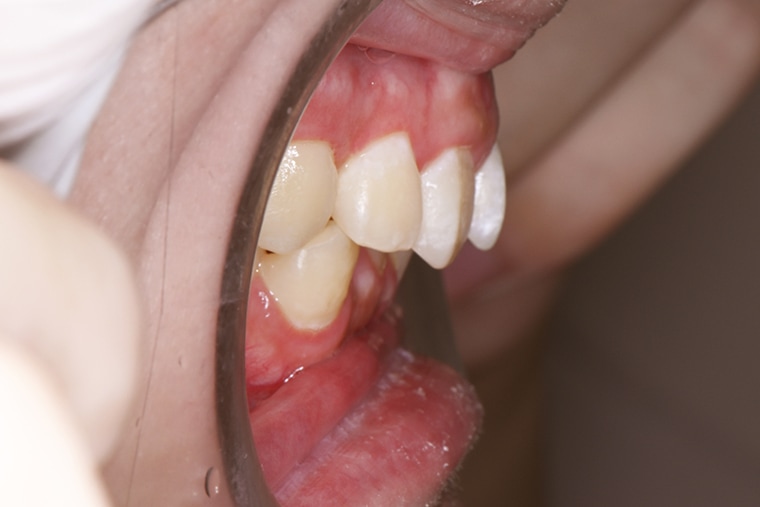

BEFORE